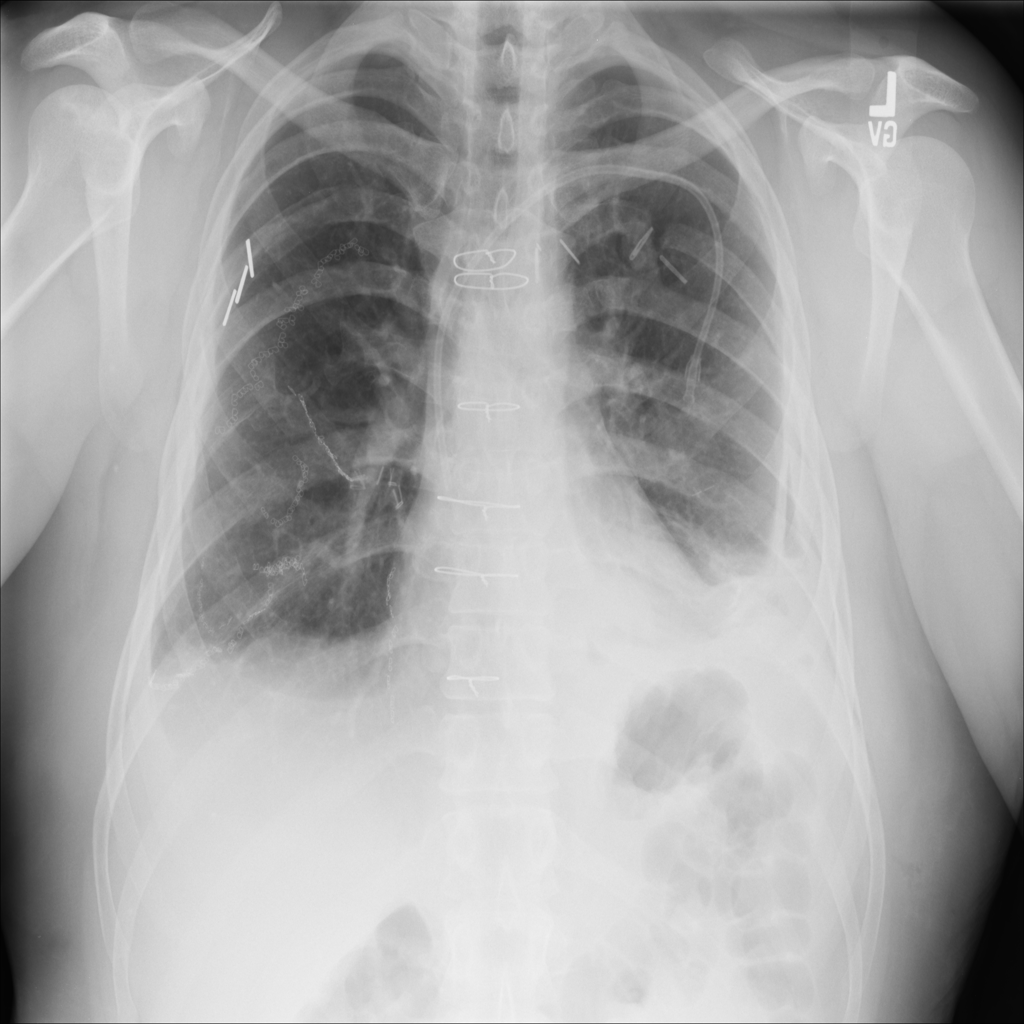

PAT-4639 · IMG-021Effusion

PAT-4639 · IMG-021

PA